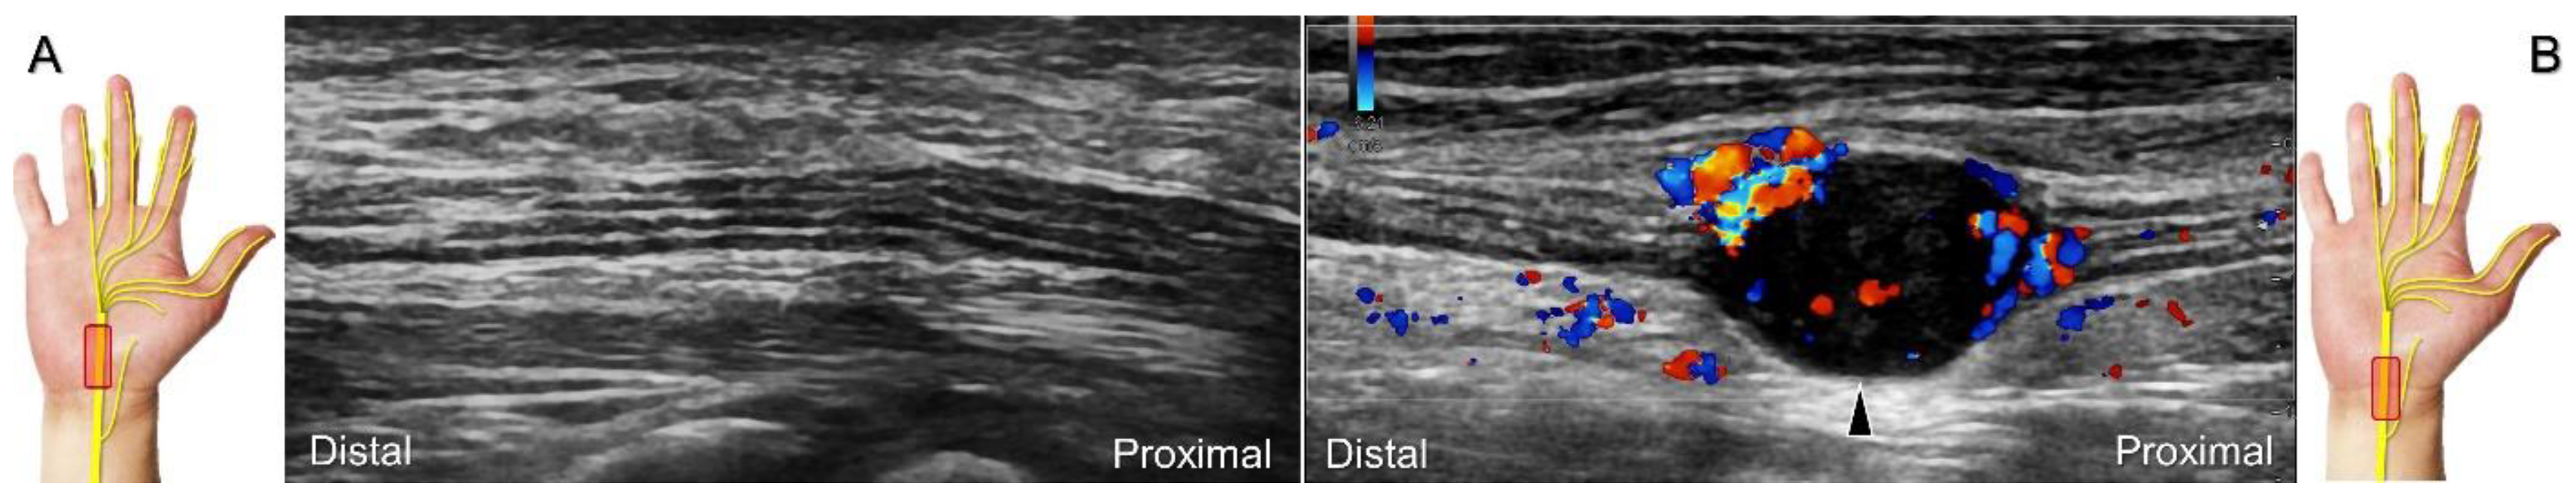

Figure 5. Comparative ultrasonography (long-axis view) between healthy (A) vs. affected (B) sides shows a schwannoma (black arrowhead) with increased intraneural vascularity.

Carpal tunnel syndrome is the most common entrapment neuropathy whereby the median nerve is entrapped by various causes, like hypertrophy of the flexor retinaculum (Figure 2C,D) and compression from the accessory muscles, swollen tendons, ganglions, and bony fractures within the tunnel. Ultrasonographic changes encompass swelling proximal to the entrapment site (Figure 3A), flattening over the entrapment site (Figure 3B), intraneural hypervascularity (Figure 3C), and focal loss of the trimline pattern (Figure 3D).

The nerve’s CSA (a cutoff value of 9–10.5 mm2) arises as the most useful parameter for the diagnosis [28], whereas its diameter, gliding resistance [29], stiffness (evaluated by sonoelastography), and intraneural vascularity (assessed by power Doppler imaging) may serve as adjuvant indicators. A bifid median nerve (Figure 4A), the presence of a persistent median artery (Figure 4B) with or without thrombosis, accessory flexor digitorum superficialis muscle (Figure 4C), laceration of the palmaris longus tendon (Figure 4D), and schwannoma (Figure 5) can be associated findings for carpal tunnel syndrome [9].